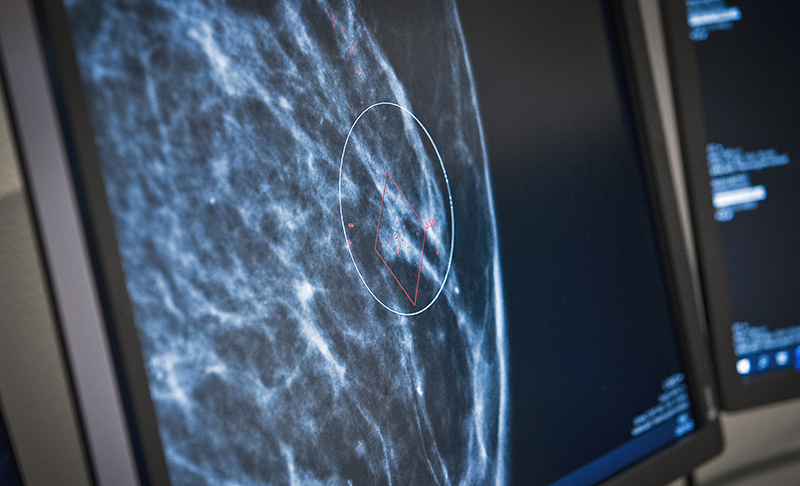

AI-verktyget effektiviserar mammografin genom att halvera antalet bröstradiologer som granskar screeningfall med låg risk för cancerfynd.

Som första region i Sverige använder Region Värmland artificiell intelligens vid mammografin på Centralsjukhuset i Karlstad. Arbetssättet frigör både värdefull tid för bröstradiologerna och medför också att färre patienter kallas på återbesök i onödan.

AI-verktyget har använts sedan 2022 och gör det möjligt att effektivisera mammografin genom att halvera antalet bröstradiologer som granskar screeningfall med låg risk för cancerfynd. Tidigare tittade två bröstradiologer på alla bilder, oavsett riskgrupp. Mikael Fredholm är medicinteknisk ingenjör och tekniskt ansvarig för införandet av AI-verktyget i Region Värmland. Han tar udden av den mystik många kanske upplever kring begreppet artificiell intelligens.

Efter beslut i hälso- och sjukvårdsledning om ordnat införande genomfördes en studie där AI-verktyget fick göra egna bedömningar efter att två bröstradiologer tittat på röntgenbilderna. AI-verktygets resultat visade sig överensstämma väldigt väl med bröstradiologernas bedömning.

AI sätter en så kallad screeningscore från 1-10 där 1 är låg risk för cancer och 10 hög. Bilderna kategoriseras sedan i två grupper: en lågriskgrupp med screeningscore 1-4 och en normalriskgrupp med screeningscore 5-10. Bilderna från lågriskgruppen granskas numer av en bröstradiolog och av AI och normalriskgruppen granskas av två bröstradiologer och AI, tidigare krävdes två radiologer för varje grupp.

– Studien visade att mindre än fem procent av cancerfallen hade en screeningscore under fem, vilket är gränsen för fall att bli enkelgranskade, säger Mikael. Det visar att AI är bra på att sortera ut de som inte är sjuka.